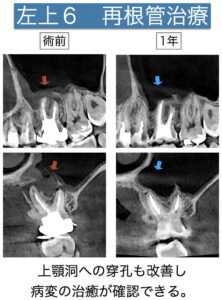

当院のCTは一般的な歯科用CTと異なり、スライス幅75μmで撮影できる特別な機能があり、通常では写らない画像上の異常を発見することができます。今まで見えていなかった病気の原因がはっきりとすることで、より正確に診断することができます。